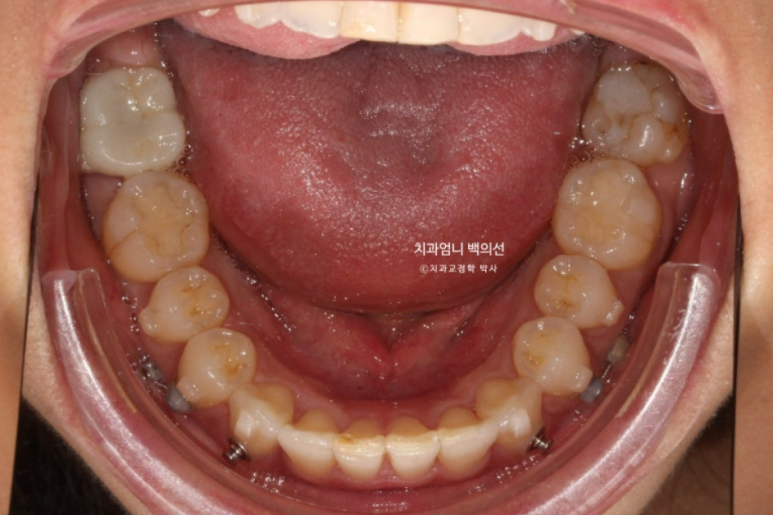

아래치열은 더 이상 고칠 것이 없어보입니다.

큰 공사가 끝났으니 이제 자잘한 마무리 공사를 합니다.

재제작 기간은 추가장치 수령까지 약 1달 걸립니다.

24년 9월부터 25년 1월까지 5개월간 추가장치를 다 낀 모습입니다.

비로소 덧니는 완벽히 제자리를 찾았지만

여전히 약 1mm 가량의 위 아래 중심선 불일치가 보여 환자분 기준 우측 가운데 앞니의 치축이 미세하게 기울어져 보입니다.